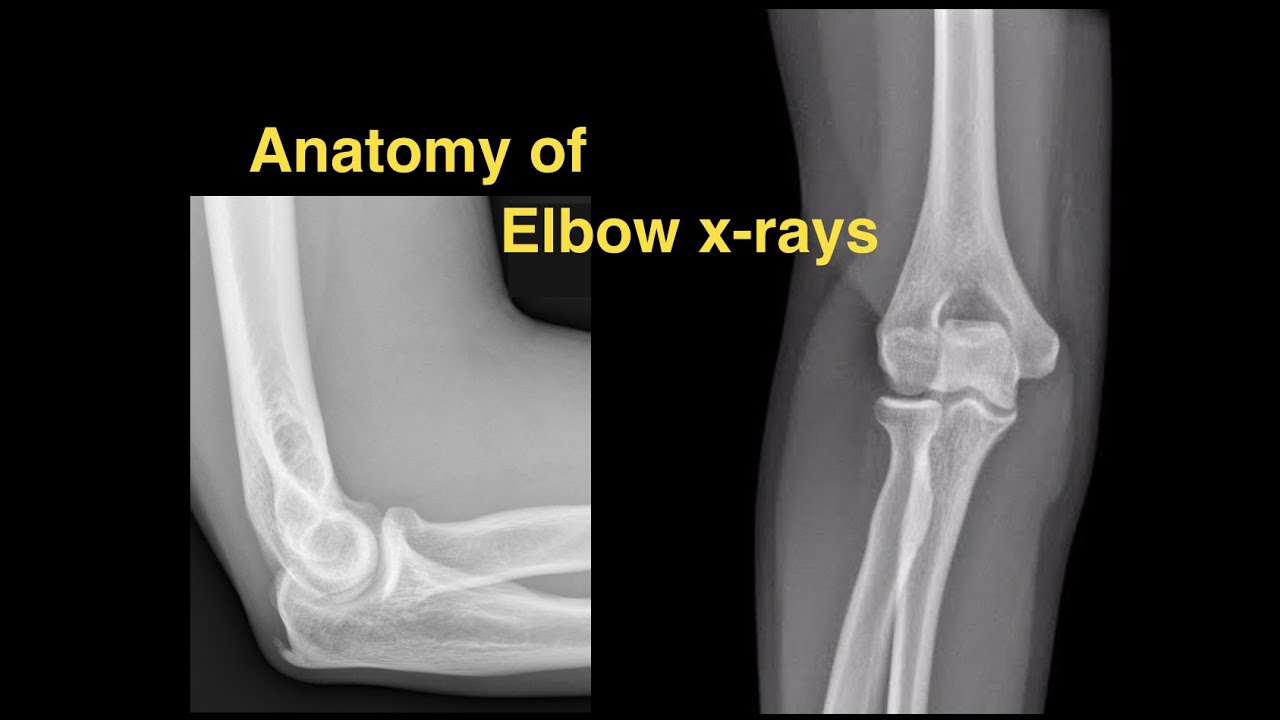

here which accommodates the coronoid process in full flexion similarly we have a radial fossa which is seen over here to accommodate the radial head in full flexion these are some of the key structures in the arab elbow region let's now look at a simple x-ray this is a plane ap x-ray in anteroposterior x-ray of the right elbow joint and we can see some of the same structures again this is the humerus which is the distal end of this bone we can also see the ulna and the radius more distally over here this is the radius

on this side and this is the ulna on this side and these three bones participate in the formation of the elbow joint which is a hinge joint the coronoid process can be seen over here and is outlined here in yellow orange color similarly the radial head is seen over here and is outlined in reddish orangish color over here these are two key structures that articulate with the distal end of the humerus to form the elbow joint or as a as known as a hinge joint the lateral epicondyle and the medial epicondyle are also seen over

here on the distal end of the humerus and over here on the lateral side of the distal end of the humerus the olecranon is seen over here which is a very interesting structure seen on the posterior side and requires a posterior vantage point view we can see it in an x-ray because the radiation goes through and through and it is overlapping with the condylar area of the humerus we will see this more clearly in a lateral view of the elbow joint in the olecranon fossa is the area on the distal humerus that accommodates this electron